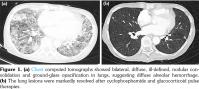

On the fifth day of hospitalization, she complained of cough and shortness of breath, and chest radiography showed consolidations in bilateral lower lung fields. Intravenous antibiotics were started for a presumed pulmonary infection. No microorganism was grown in the sputum, blood or urine, and further microbiologic tests were all negative for cytomegalovirus, aspergillus and Pneumocystis jirovecii. High- dose glucocorticoid was added for suspected concurrent lung involvement in newly developed SLE, but symptoms and lung infiltrations on computed tomography (Figure 1a) worsened and black-colored crusted patches occurred on the right ala of her nose (Figure 2a). On the 17th hospital day, the patient was transferred to the intensive care unit and placed on mechanical ventilator due to expected impending respiratory failure. A bronchoscopic exam showed bloody bronchoalveolar lavage fluid. Biopsy of the nasal lesion and histopathology confirmed mucormycosis

(Figure 2b). Plasma exchange and intravenous immunoglobulin therapy were performed with liposomal amphotericin B. However, her respiration was not improved and the endotracheal tube was frequently blocked because of persistent DAH. Notwithstanding the risk of the concurrent infection aggravation, cyclophosphamide and glucocorticoid pulse therapy were added for the management of the refractory DAH. Three cycles of cyclophosphamide pulse therapies (intravenous cyclophosphamide 500 mg with methylprednisolone 1 g) were administered with a surgical debridement of the nasal mucormycosis lesions on the 39th hospital day (Figure 2c). Her respiration stabilized and the lung lesion gradually resolved with the cyclophosphamide pulse therapies (Figure 1b). The patient eventually recovered after three months of intensive care unit care.